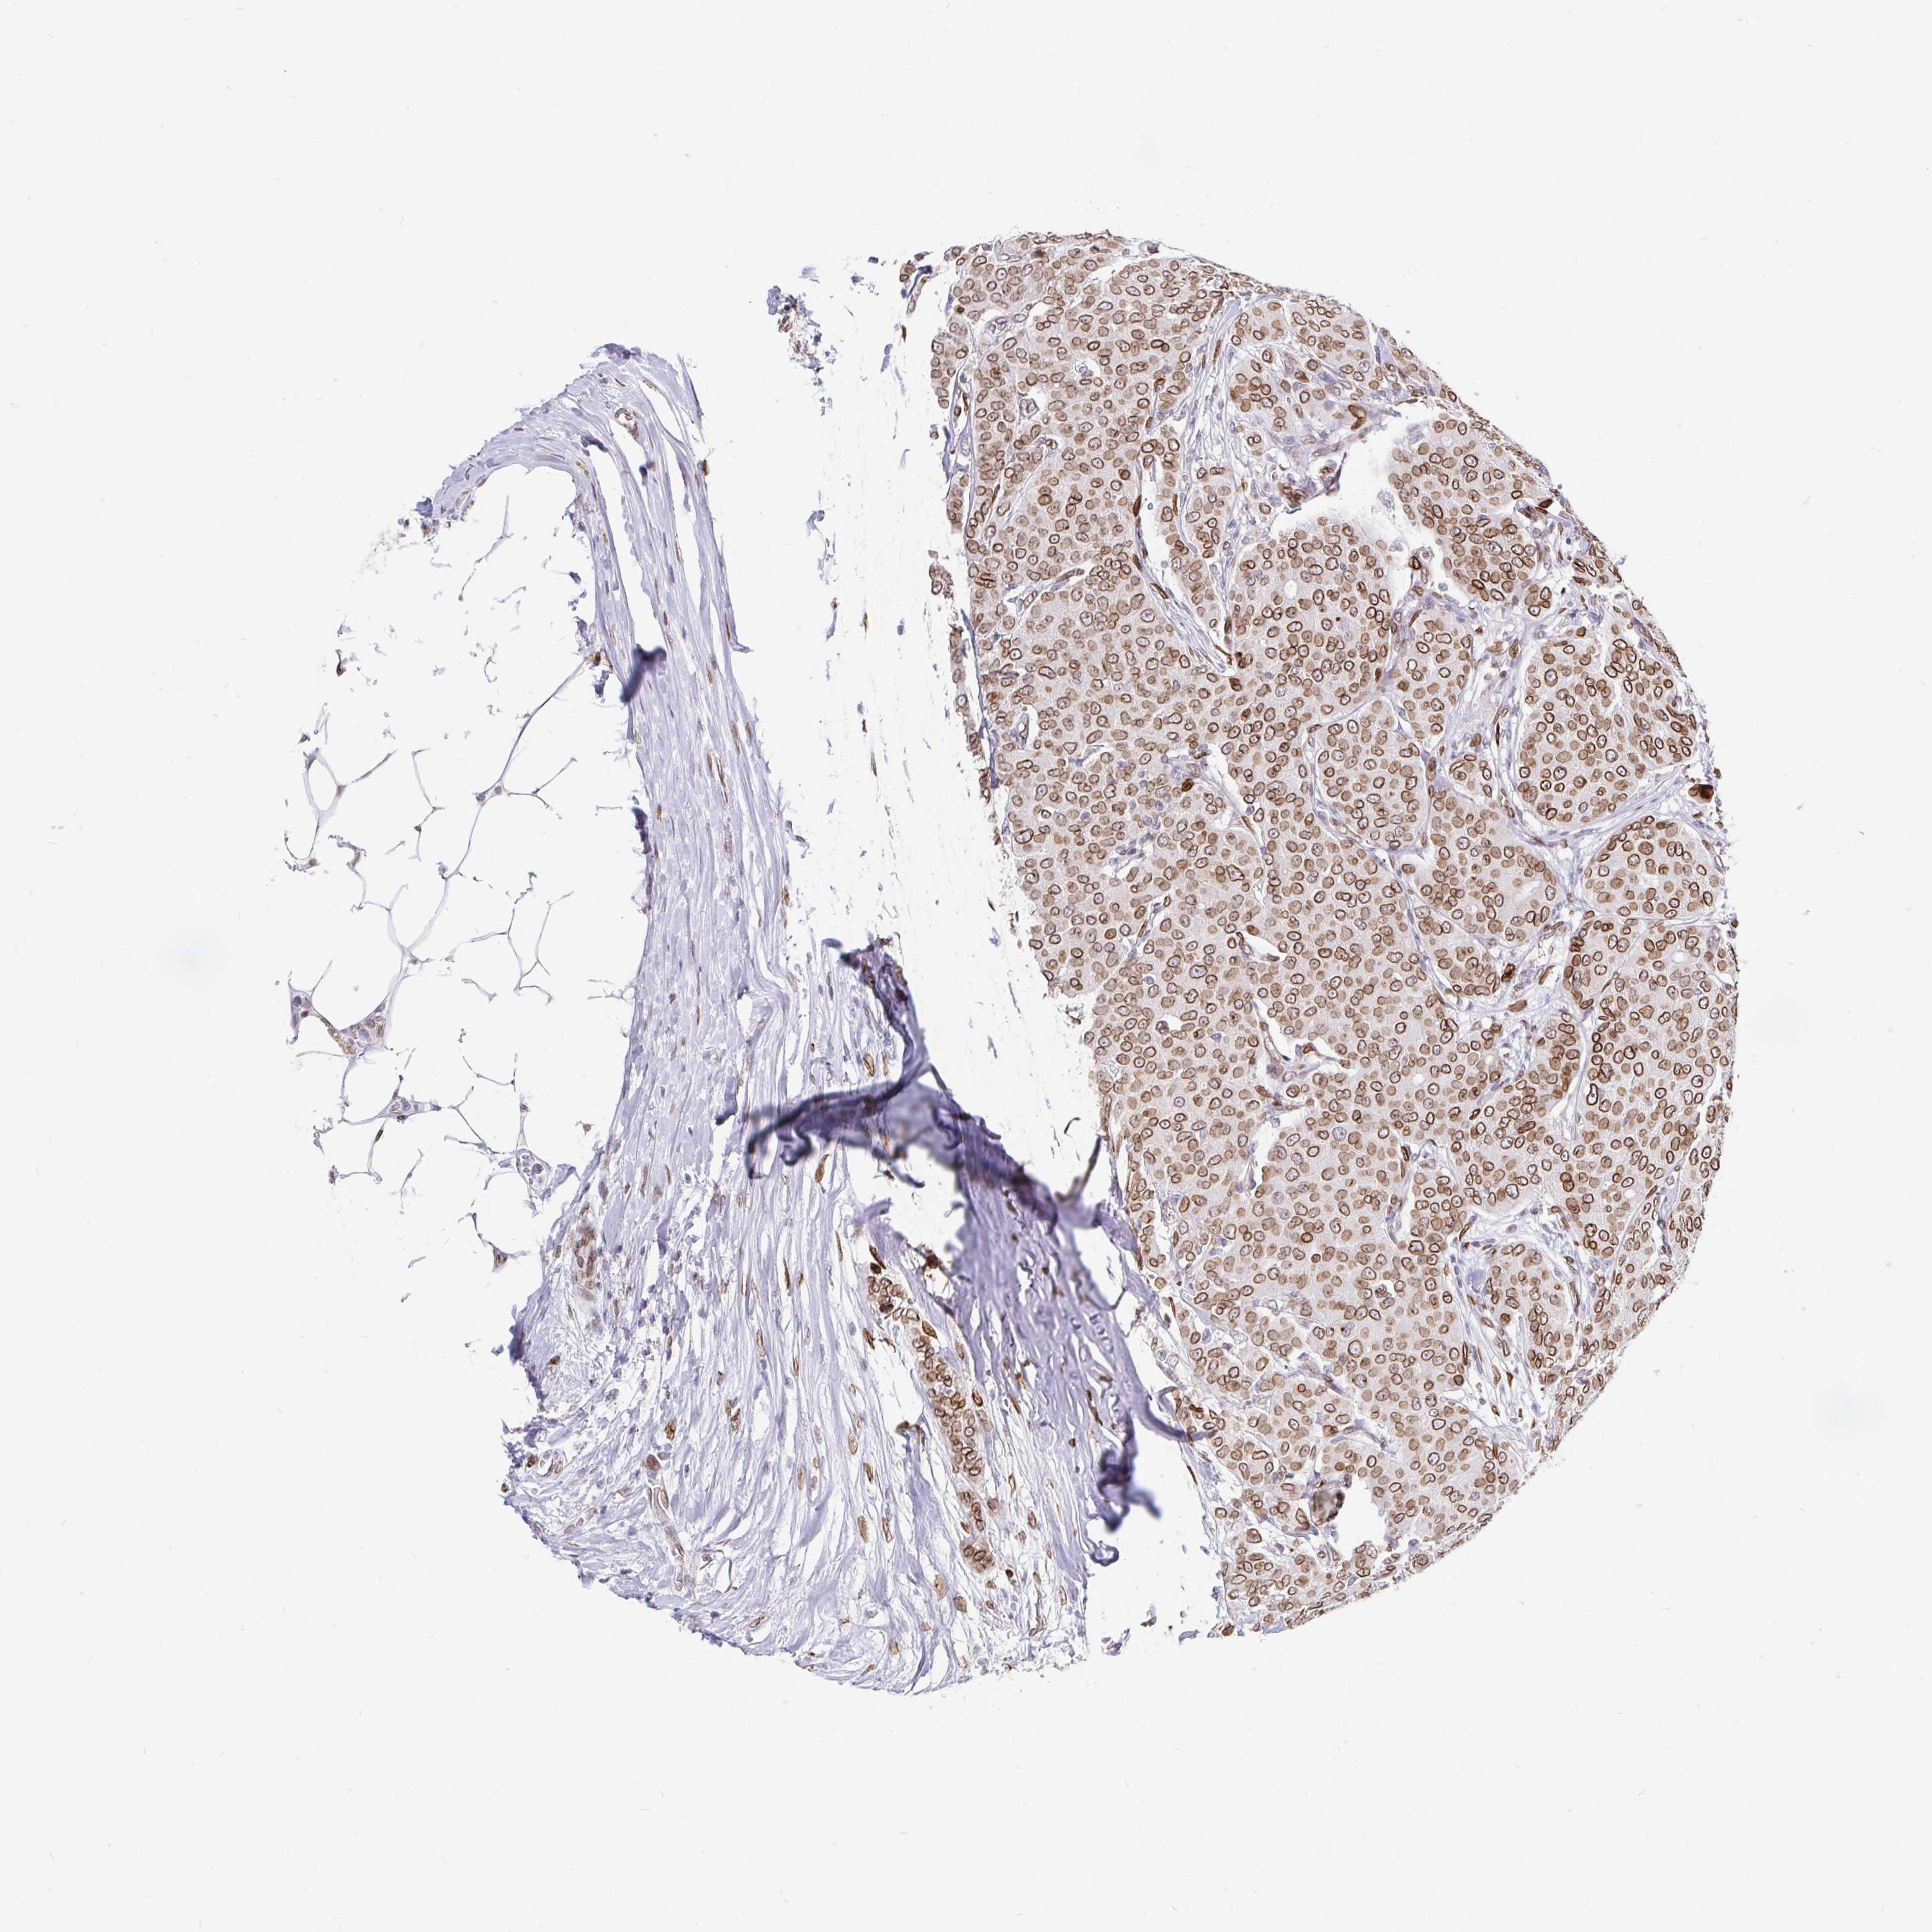

BRCA TCGA BRCA VALIDATION PROTEIN EXPRESSION